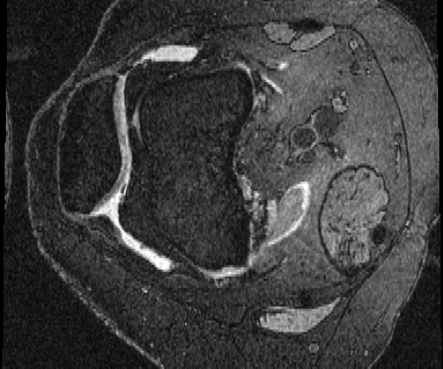

OAI Knee MRI We train and test on the split published with [22], with 2532 training examples and 301 test pairs from the Osteoarthritis Initiative (OAI) [16]444https://nda.nih.gov/oai. We evaluate using the mean Dice score of tibial and fibial cartilage. To compare directly to [22, 7, 23] we train and evaluate at [80x192x192].

| Moving Image | Warped Image | Fixed Image | Moving Image | Warped Image | Fixed Image |